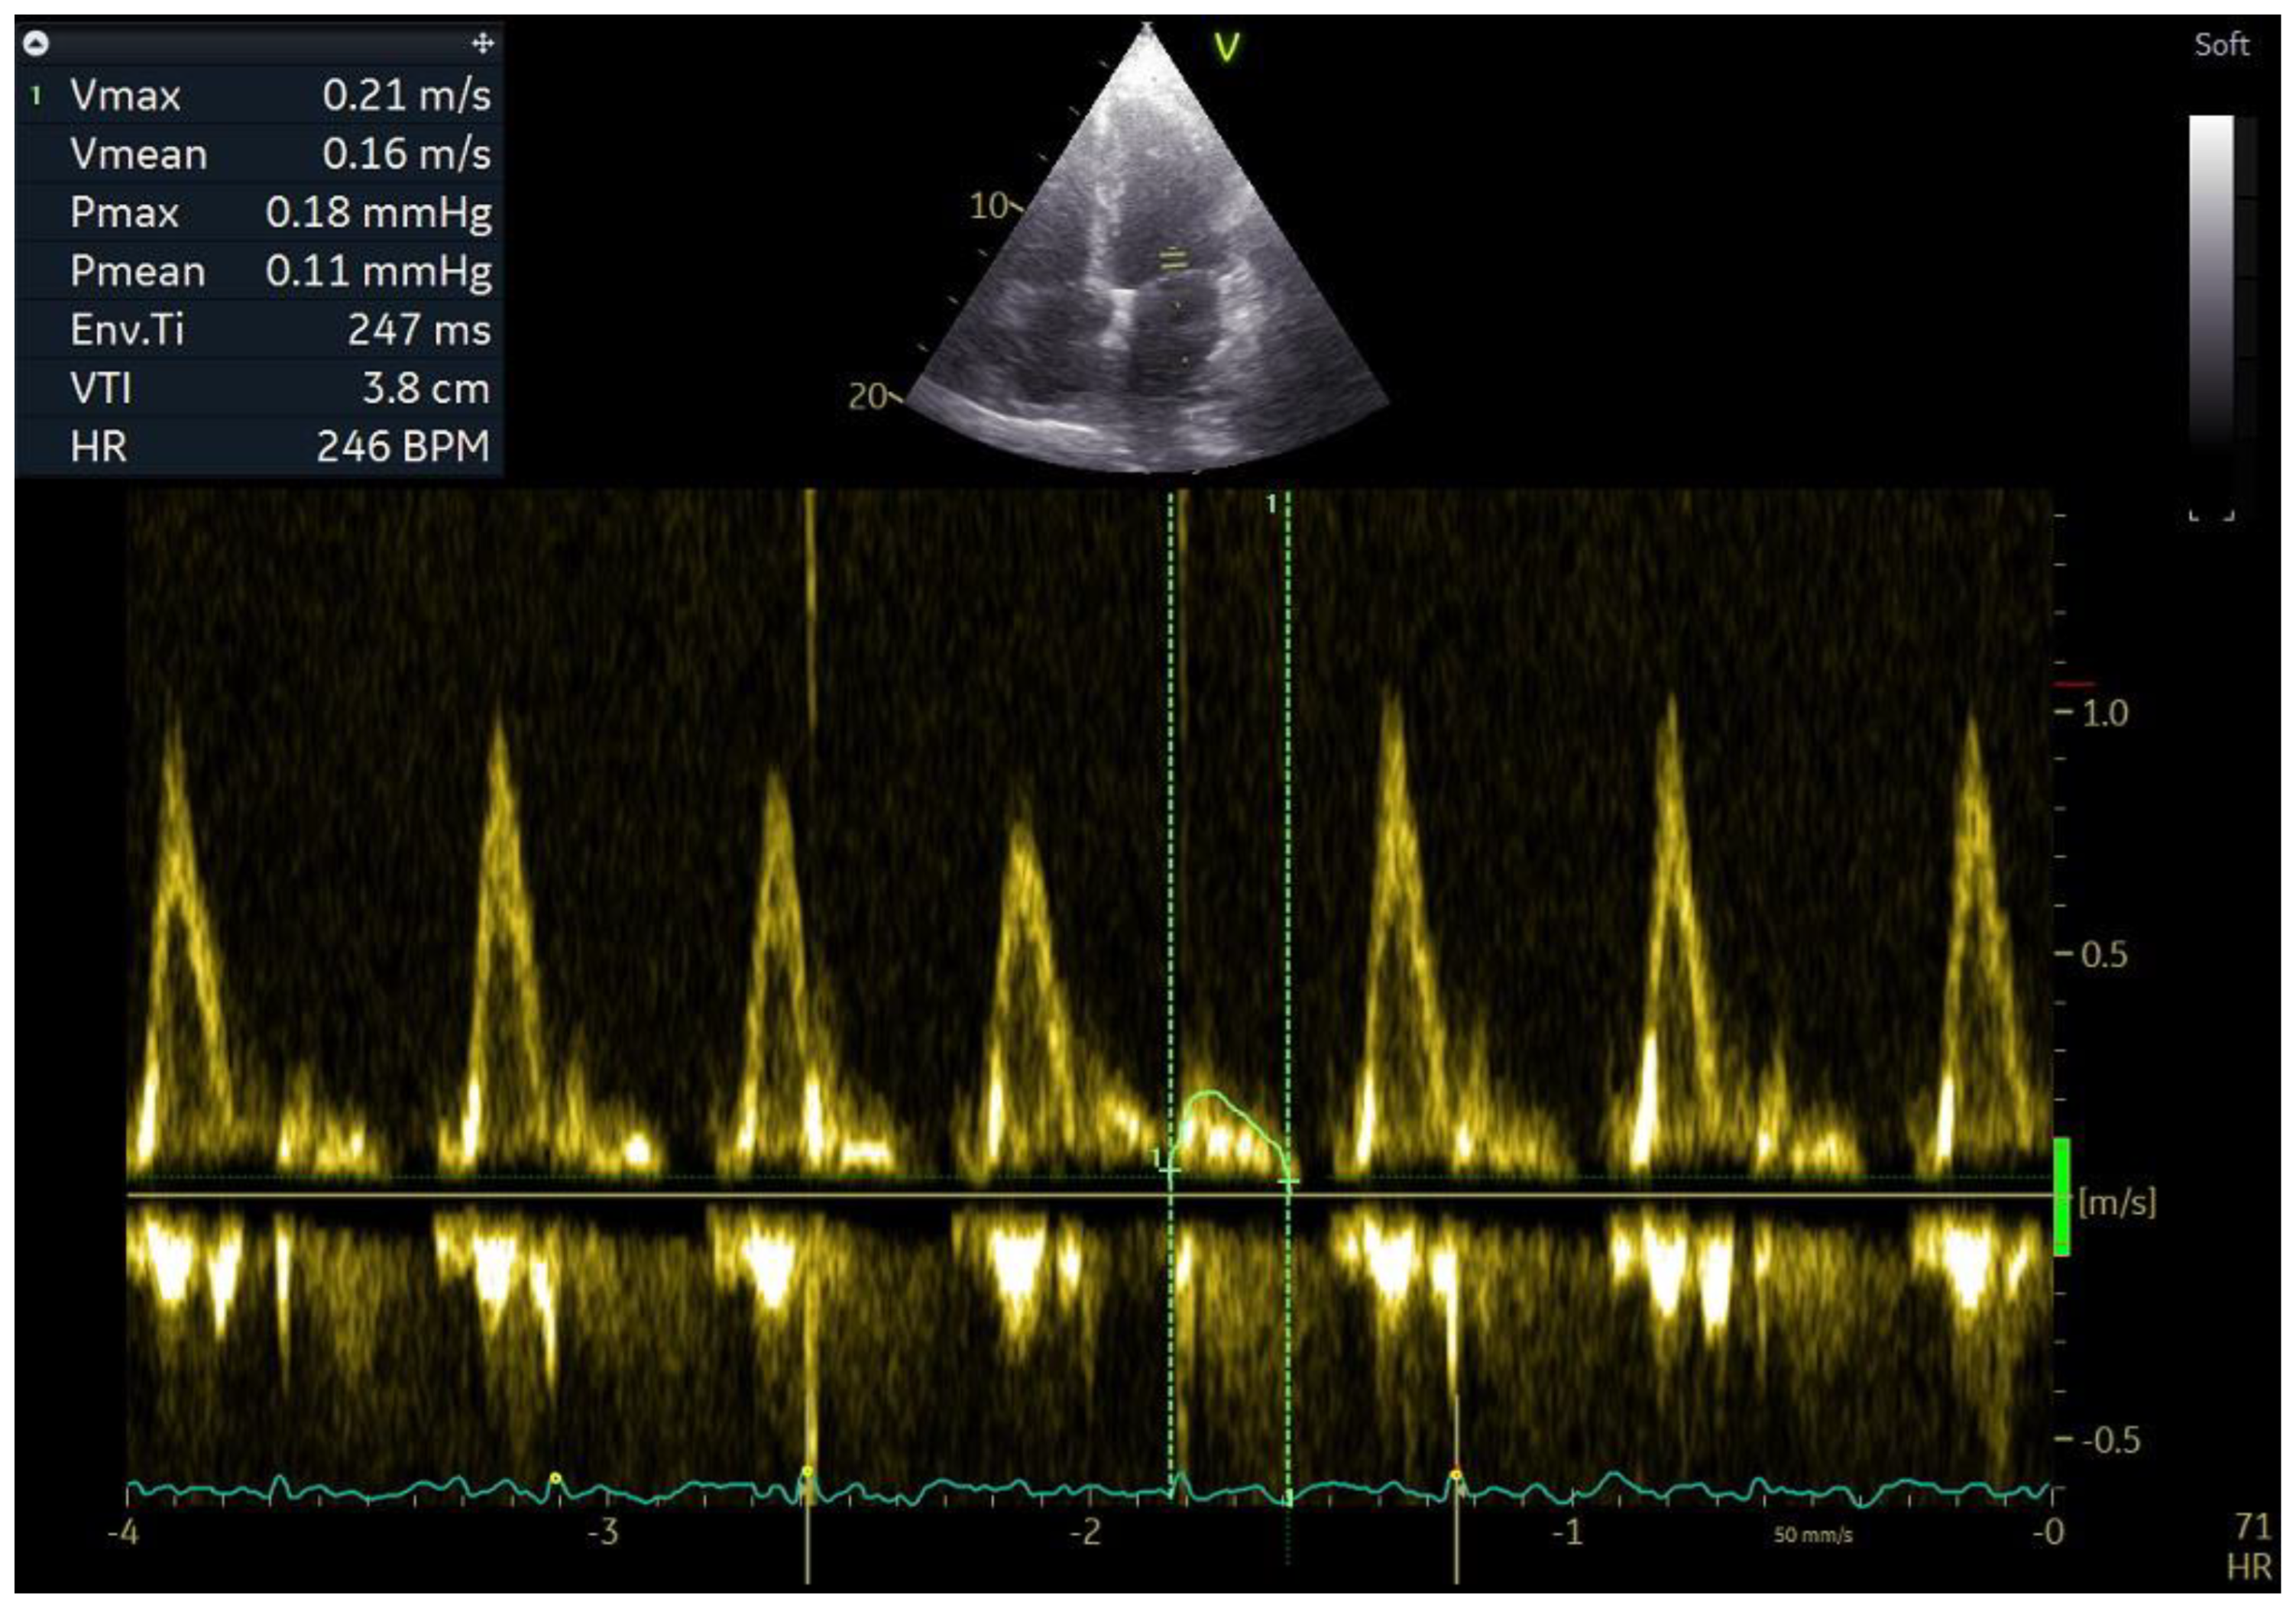

5. Electrical Remodelling

The type of remodelling that occurs first, and is also the least visible and difficult to visualise with echocardiography, is electrical remodelling. Electrical remodelling of the atrial walls is an expression of disorders in intercellular connections, change in ion channels, progressive LA wall fibrosis, and abnormalities in the conduction of electrical stimuli between the cells of the atrial wall, which results in slowing down of electrical stimuli conduction and the development of micro-re-entry substrate [61,62]. A lack of balance between collagen synthesis and degradation leads to myolysis and the development of atrial fibrosis, which in turn affects the electromechanical function of the LA, manifested by a longer atrial conduction time [63,64]. Currently, the only echocardiographic parameter that depends on electrical remodelling but also on structural remodelling is total atrial conduction time (TACT) (Figure 7). TACT is affected by both slowing down of the electrical stimuli conduction in the atrial wall, i.e., electrical remodelling, and by the length of the path that electrical stimuli must travel, i.e., enlargement of the right and left atrial cavity, which is an expression of structural remodelling. The delay between the P wave in the electrocardiogram from lead I or II and mechanical LA activation measured by tissue Doppler echocardiography, called PA-TDI, provides a reliable estimate of total atrial activation time, reflecting the degree of atrial fibrosis in biopsy samples [65]. In a study by Leung et al., PA-TDI was shown to be significantly higher in patients with AF compared to those without AF [66]. TACT prolongation reflects the slowing down of conduction and dilation of the atria and identifies individuals prone to developing atrial fibrillation [67,68].

Figure 7. Total atrial conduction time (TACT). PA-TDI 160 ms. PA-TDI is the time interval between the onset of the P wave in electrocardiogram in lead I or II and the peak of the a’ wave on the atrial tissue Doppler velocity curve from the lateral left atrial wall. Pulsed-wave tissue Doppler of mitral annulus velocity in the apical four-chamber projection during sinus rhythm. a’, late lateral mitral annulus velocity; e’, early lateral mitral annulus velocity; s’, systolic mitral annulus velocity.